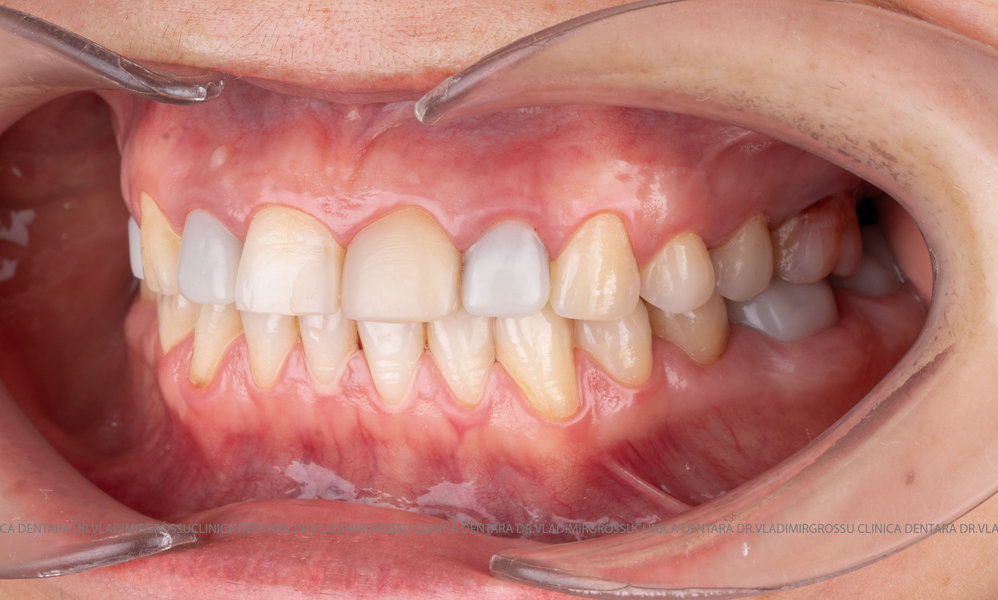

Restaurări cu coroane din zirconiu vs fațete ceramice

Atât fațetele ceramice (Emax sau 360) cât și coroanele din zirconiu sunt soluții estetice eficiente. Fațetele sunt indicate pacienților cu o poziție dentară relativ uniformă și dinți vitali, deoarece implică șlefuirea minimală a smalțului (0,4–0,7 mm) și fixarea adezivă sub coferdam. În cazurile cu dinți tratați endodontic, coroane pigmentate, proteze pe implanturi sau când este necesară o creștere semnificativă a ocluziei, se preferă coroanele din zirconiu.

Stabilirea lungimii și formei dinților pentru efectul de întinerire

Parametrii estetici ai dinților – lungime, lățime și formă – se adaptează caracteristicilor anatomice individuale ale pacientului. Orizontul zâmbetului corespunde, în general, orizontului pupilelor, iar lungimea dinților este influențată de scheletul maxilarului superior, poziția și mobilitatea buzei superioare. Totuși, frumusețea este subiectivă și personalizată.